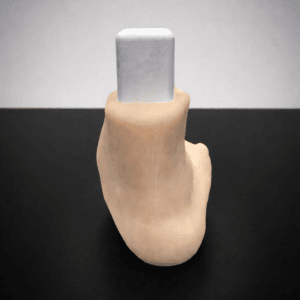

| Pathology | Pes Cavus |

| Procedure | Cole Osteotomy, Dwyer, Lateralizing Calcaneal Osteotomy, Metatarsal Dorsiflexion Osteotomy |

| Area | Midfoot |

| Modularity | Single-piece |

| Material | Opaque |

Pes Cavus – Bone Model